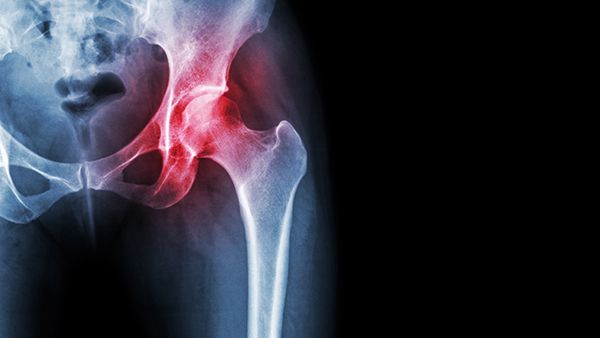

Diagnostic injections aren't just treatment, Dr. Domb explains how they're a tool for pinpointing exactly where your pain is coming from 💉 #orthopedicsurgeon #diagnostic #injections #hippain youtube.com/watch?v=Iylkib…

Dr. Domb is a nationally recognized orthopaedic surgeon specializing in sports medicine and hip surgery.